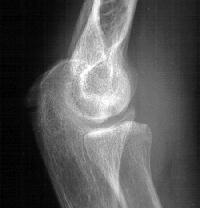

Plain films show humeral osteophytes and posttraumatic changes of the capitellum and radial head.